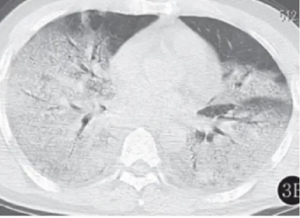

▲SARS患者的"白肺"(图片来自网络)

肺纤维化是肺脏受到伤害后,人体修复产生的结果。倘若正常人的肺是"嫩丝瓜",那么纤维化的肺就像干透了的丝瓜一样,整个肺会变得像木头般没有弹性,呼吸功能明显减弱,严重者各种肺部组织几乎坏死,最终不能自主呼吸而死亡。